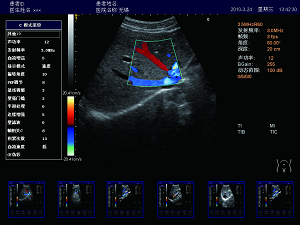

精確血流成像

智能識別血流運動和組織運動,使血流更充盈,組

織邊界更清晰。

肝臟 脾臟 多普勒血流

高效的多譜勒技術

多普勒幀相關 血流圖像更平滑更清晰。

多普勒快速優(yōu)化 對于危重病人,兒童可以在短時間內(nèi)獲得最佳的血流成像。

壁濾波器 增強血流邊緣清晰度,產(chǎn)生精準的發(fā)射波形,達到最佳匹配效果,提高全聲場的回波質(zhì)量。